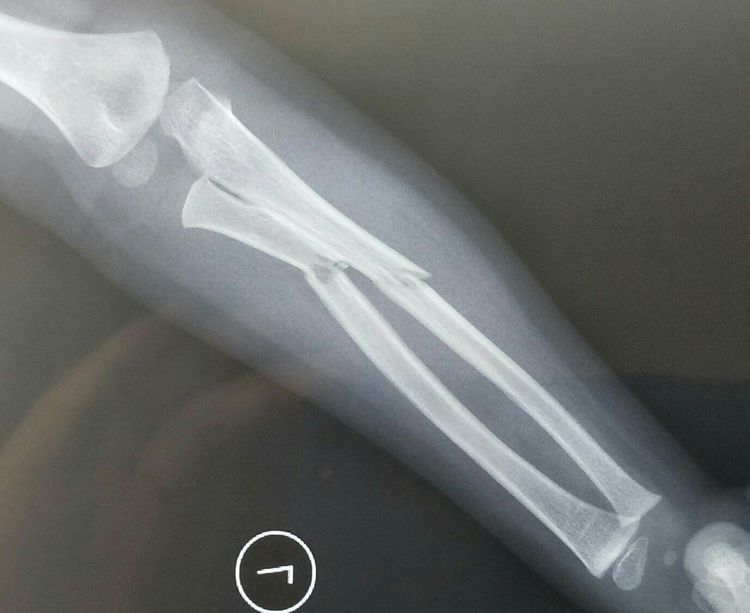

患儿张×,男性,3岁2个月,病案号(2003072528),主因左前臂摔伤后肿痛、畸形、活动受限3小时入院,查体:左前臂肿胀、畸形,左前臂旋转受限,左肘关节屈伸活动受限,左手各指活动尚可。

扎鲁特旗人民医院左前臂正侧位片示:左前臂双骨折,骨折端成角移位明显,入院诊断:左前臂双骨折,因骨折端成角移位明显,而且考虑桡骨小头可能存在半脱位,手法复位失败率高,故拟行手术治疗。

术后拍片复查,尺桡骨骨折端复位良好,内固定克氏针位置良好,均在髓腔内。

术后一个月拍片复查,内固定克氏针位置良好,骨折端对位对线好,骨折端骨痂生长。